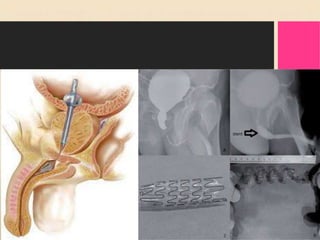

2. Transurethral Needle

Ablation.

• Transurethral needle ablation (TUNA) is

another procedure that increases the

temperature of prostate tissue, thus causing

localized necrosis. TUNA differs from TUMT

in that low-wave radiofrequency is used to

heat the prostate. Only prostate tissue in

direct contact with the needle is affected,

thus allowing greater precision in removal of

the target tissue.

• The extent of tissue removed by this

process is determined by the amount

of tissue contact (needle length),

amount of energy delivered, and

duration of treatment.

• This procedure is performed in an outpatient

unit or physician’s office using local

anesthesia and IV or oral sedation. The

TUNA procedure lasts approximately 30

minutes. The patient typically experiences

little pain with an early return to regular

activities.

• Complications include urinary retention,

UTI, and irritative voiding symptoms (e.g.,

frequency, urgency, dysuria). Some

patients require a urinary catheter for a

short time. Patients often have hematuria

for up to a week.